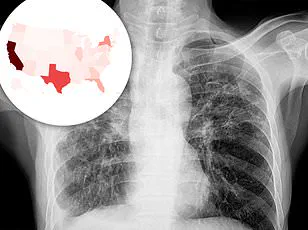

The latest data from the Centers for Disease Control and Prevention (CDC) shows that in 2024, the U.S. provisionally recorded 10,347 tuberculosis cases—an 8% increase from the previous year and the highest tally since 2011.

The rise in tuberculosis cases is not confined to a single region.

According to the CDC, 80% of U.S. states have seen an increase in tuberculosis prevalence since 2020.